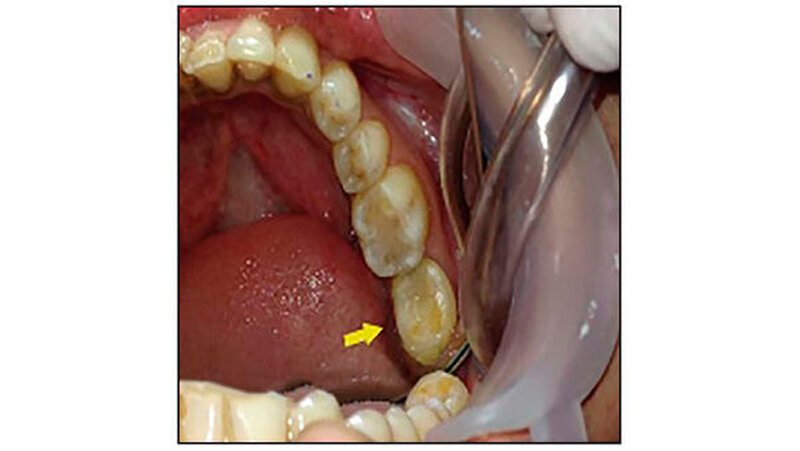

Zahn 38 wurde in das vorbereitete "Bett" von 37 transplantiert. Mit Nahtmaterial (Nähte India Pvt Ltd, Indien) stabilisierten die Zahnärzte die Position des transplantierten Zahns (Abbildung 3). Die intraradikuläre Schienung erfolgte mit formbarem kieferorthopädischem Draht (Tru-Bogen, Ormco Ltd., USA). Anhand eines postoperativen Röntgenbilds wurde die neue Position des 38 überprüft. Zur Unterstützung des Heilungsprozesses bekam die Patientin einen parodontalen Wundverband (Coe-Pack, G C Indien) angelegt.